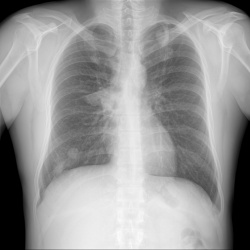

Добрый день. Подскажите пожалуйтса как описать в нижних отделах левого легкого.. как образование слева ?